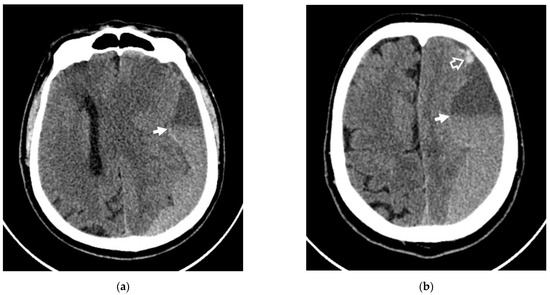

- Are there any differences in the concentrations of angiogenesis factors in the bloods between patients who have repeated hemorrhages in the area of CSDH (rebleeding) and patients with a fairly homogeneous structure of the hematoma according to non-contrast computed tomography (NCCT)?